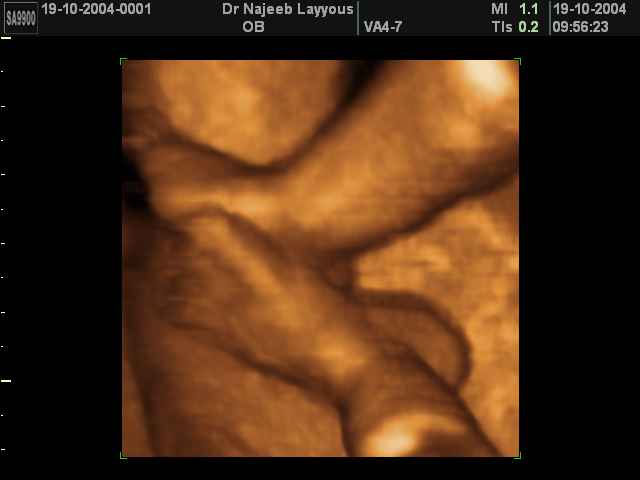

- 3D Fetal Limbs Ultrasound Scan Photos